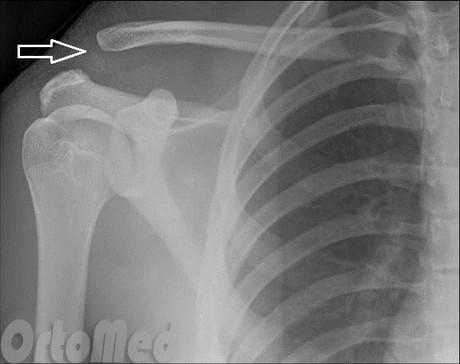

Данные по рентгену

При растяжении первого типа отсутствуют смещения на рентгене, при растяжении второго типа латеральный конец ключицы выше акромиона, но не смещен на 100%. При травме третьего типа субтотальный разрыв связок и 100% смещение на рентгене.

Травма 5-го типа

Преувеличенный верхний вывих акромиально-ключичного сустава от 100% до 300% на рентгенограмма (смотри на рисунке выше)

Расстояние до СС-связки увеличилось в два-три раза.

Диагноз вывиха акромиального конца ключицы

Диагноз вывиха акромиального конца ключицы иногда очень прост и все очевидно при осмотре, а иногда приходится решать целую головоломку. Наиболее оптимальным и распространенным способом диагностики является рентгенография. Стоит сказать, что, как не бывает одинаковых людей, так и не бывает одинаковых ключиц. Чаще всего причиной ложного диагноза индивидуальные особенности акромиально-ключичного сустава.

Поэтому целесообразно выполнять рентгенограмму не одного плеча, а двух сразу - что позволит оценить нормальное строение противоположной ключицы.

В сомнительных случаях иногда выполняют функциональную рентгенографию - в руку берут груз, который оттягивает ее вниз и вывих становится более очевидным.

Для подстверждения диагноза выполняется рентгенография плечевого сустава. На рентгенограмме четко видно, если произошел вывих акромиального конца ключицы.

Для постановки диагноза и для определения степени повреждения акромиально-ключичного сочленения наиболее информативным методом исследования является рентген.

На рентгене при первой степени разрыва акромиально-ключичного сочленения будет видно расхождение между ключицей и акромионом.

При второй степени мы видим выступание ключицы над акромионом на расстояние не более половины ее диаметра.

При третьей степени ключица выступает над лопаткой на полный свой диаметр и даже более того.

Рис. 1- Разрыв акромиально-ключичного сочленения.

Наиболее распространенная причина вывиха акромиально-ключичного сочленения - это прямое падение на плечо . При таком падении повреждаются связки, окружающие и стабилизирующие акромиально-ключичное сочленение.

Если удар достаточно сильный, происходит разрыв связок, отходящих от нижней стороны ключицы. Это вызывает "разъединение" ключицы и лопатки (рис.1). Лопатка смещается вниз под весом руки, в результате чего появляется "шишка", или бугорок, над плечом.

- Легкий вывих плеча приводит к растяжению связок акромиально-ключичного сочленения без смещения ключицы и на рентгеновском снимке выглядит нормально.

- При более серьезном повреждении происходит разрыв связок акромиально-ключичного сочленения и растяжение или небольшой надрыв клювовидно-ключичной связки со смещением ключицы.

- В наиболее серьезных случаях при вывихе плеча происходит полный разрыв как связок акромиально-ключичного сочленения, так и клювовидно-ключичной связки, в результате чего акромиально-ключичное сочленение сильно деформируется.

Данную травму легко диагностировать, если происходит деформация (смещение). Если деформация невыраженная, диагностировать повреждение врачу помогает локализация боли и рентгеновский снимок. Иногда наличие груза в руке у пациента усиливает смещение, что помогает лучше увидеть повреждение на рентгеновском снимке.